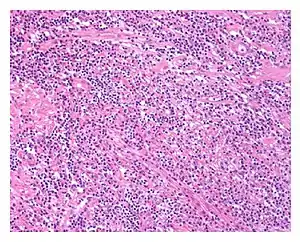

| Low power view of IgG4-related prostatitis. The prostatic stroma shows a dense inflammatory infiltrate and fibrosis (H&E, 100x) | |

The diagnosis of IgG4-related prostatitis could be made from histological examination if prostate biopsy or surgery has been performed.[6] The hallmark histopathological features of established IgG4-related disease are storiform fibrosis, a dense lymphoplasmacytic (lymphocytes and plasma cells) infiltrate rich in IgG4-positive plasma cells, and obliterative phlebitis.[7]